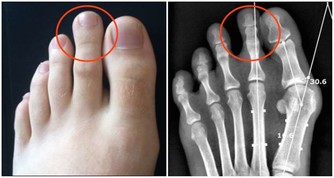

才發現原來這是扁桃腺結石,

他耐心的用畫圖方式告訴我結石藏在扁桃腺的隱窩,不易清除,

「扁 桃體結石引起的口臭並不少見,大人小孩都可能會出現」,北京中醫醫院耳鼻喉科副主任醫師姜志輝解釋。 扁桃體是人體的免疫器官,位於口咽側壁,包含有 很多隱窩,其中位於扁桃體上極的上隱窩就容易出現結石。 正常情況下扁桃腺隱窩沒有分泌物。 當扁桃體出現急慢性炎症時,就會有脫落上皮、大量淋巴細胞, 白細胞、以及各種致病菌自隱窩排出,若隱窩口堵塞而引起分泌物堆積,時間長了還會導致一些鎂、鈣等無機鹽沉積而引起結石。 這些腐敗的分泌物就會引起口 臭。

另 外,蔡立泰醫師也表示,扁桃腺結石通常看起來像白色或微黃色的小石頭,有時候吐出來時,可以把這些小石頭壓碎,並出現臭臭的味道。扁桃腺結石目前 大多認為是由食物的殘渣及壞菌卡在扁桃腺表面的隱窩中所形成。有些人會感覺到喉嚨卡卡的感覺,嚴重的患者更可能出現頭痛、咽喉疼痛、吞嚥困難、耳朵痛癢、 甚至嘔吐等情形。也因為這些細菌和食物的殘渣以及部分壞死組織的鈣化,所以可能在講話時散發出一些腐爛的臭味,也就是我們所謂的口臭。